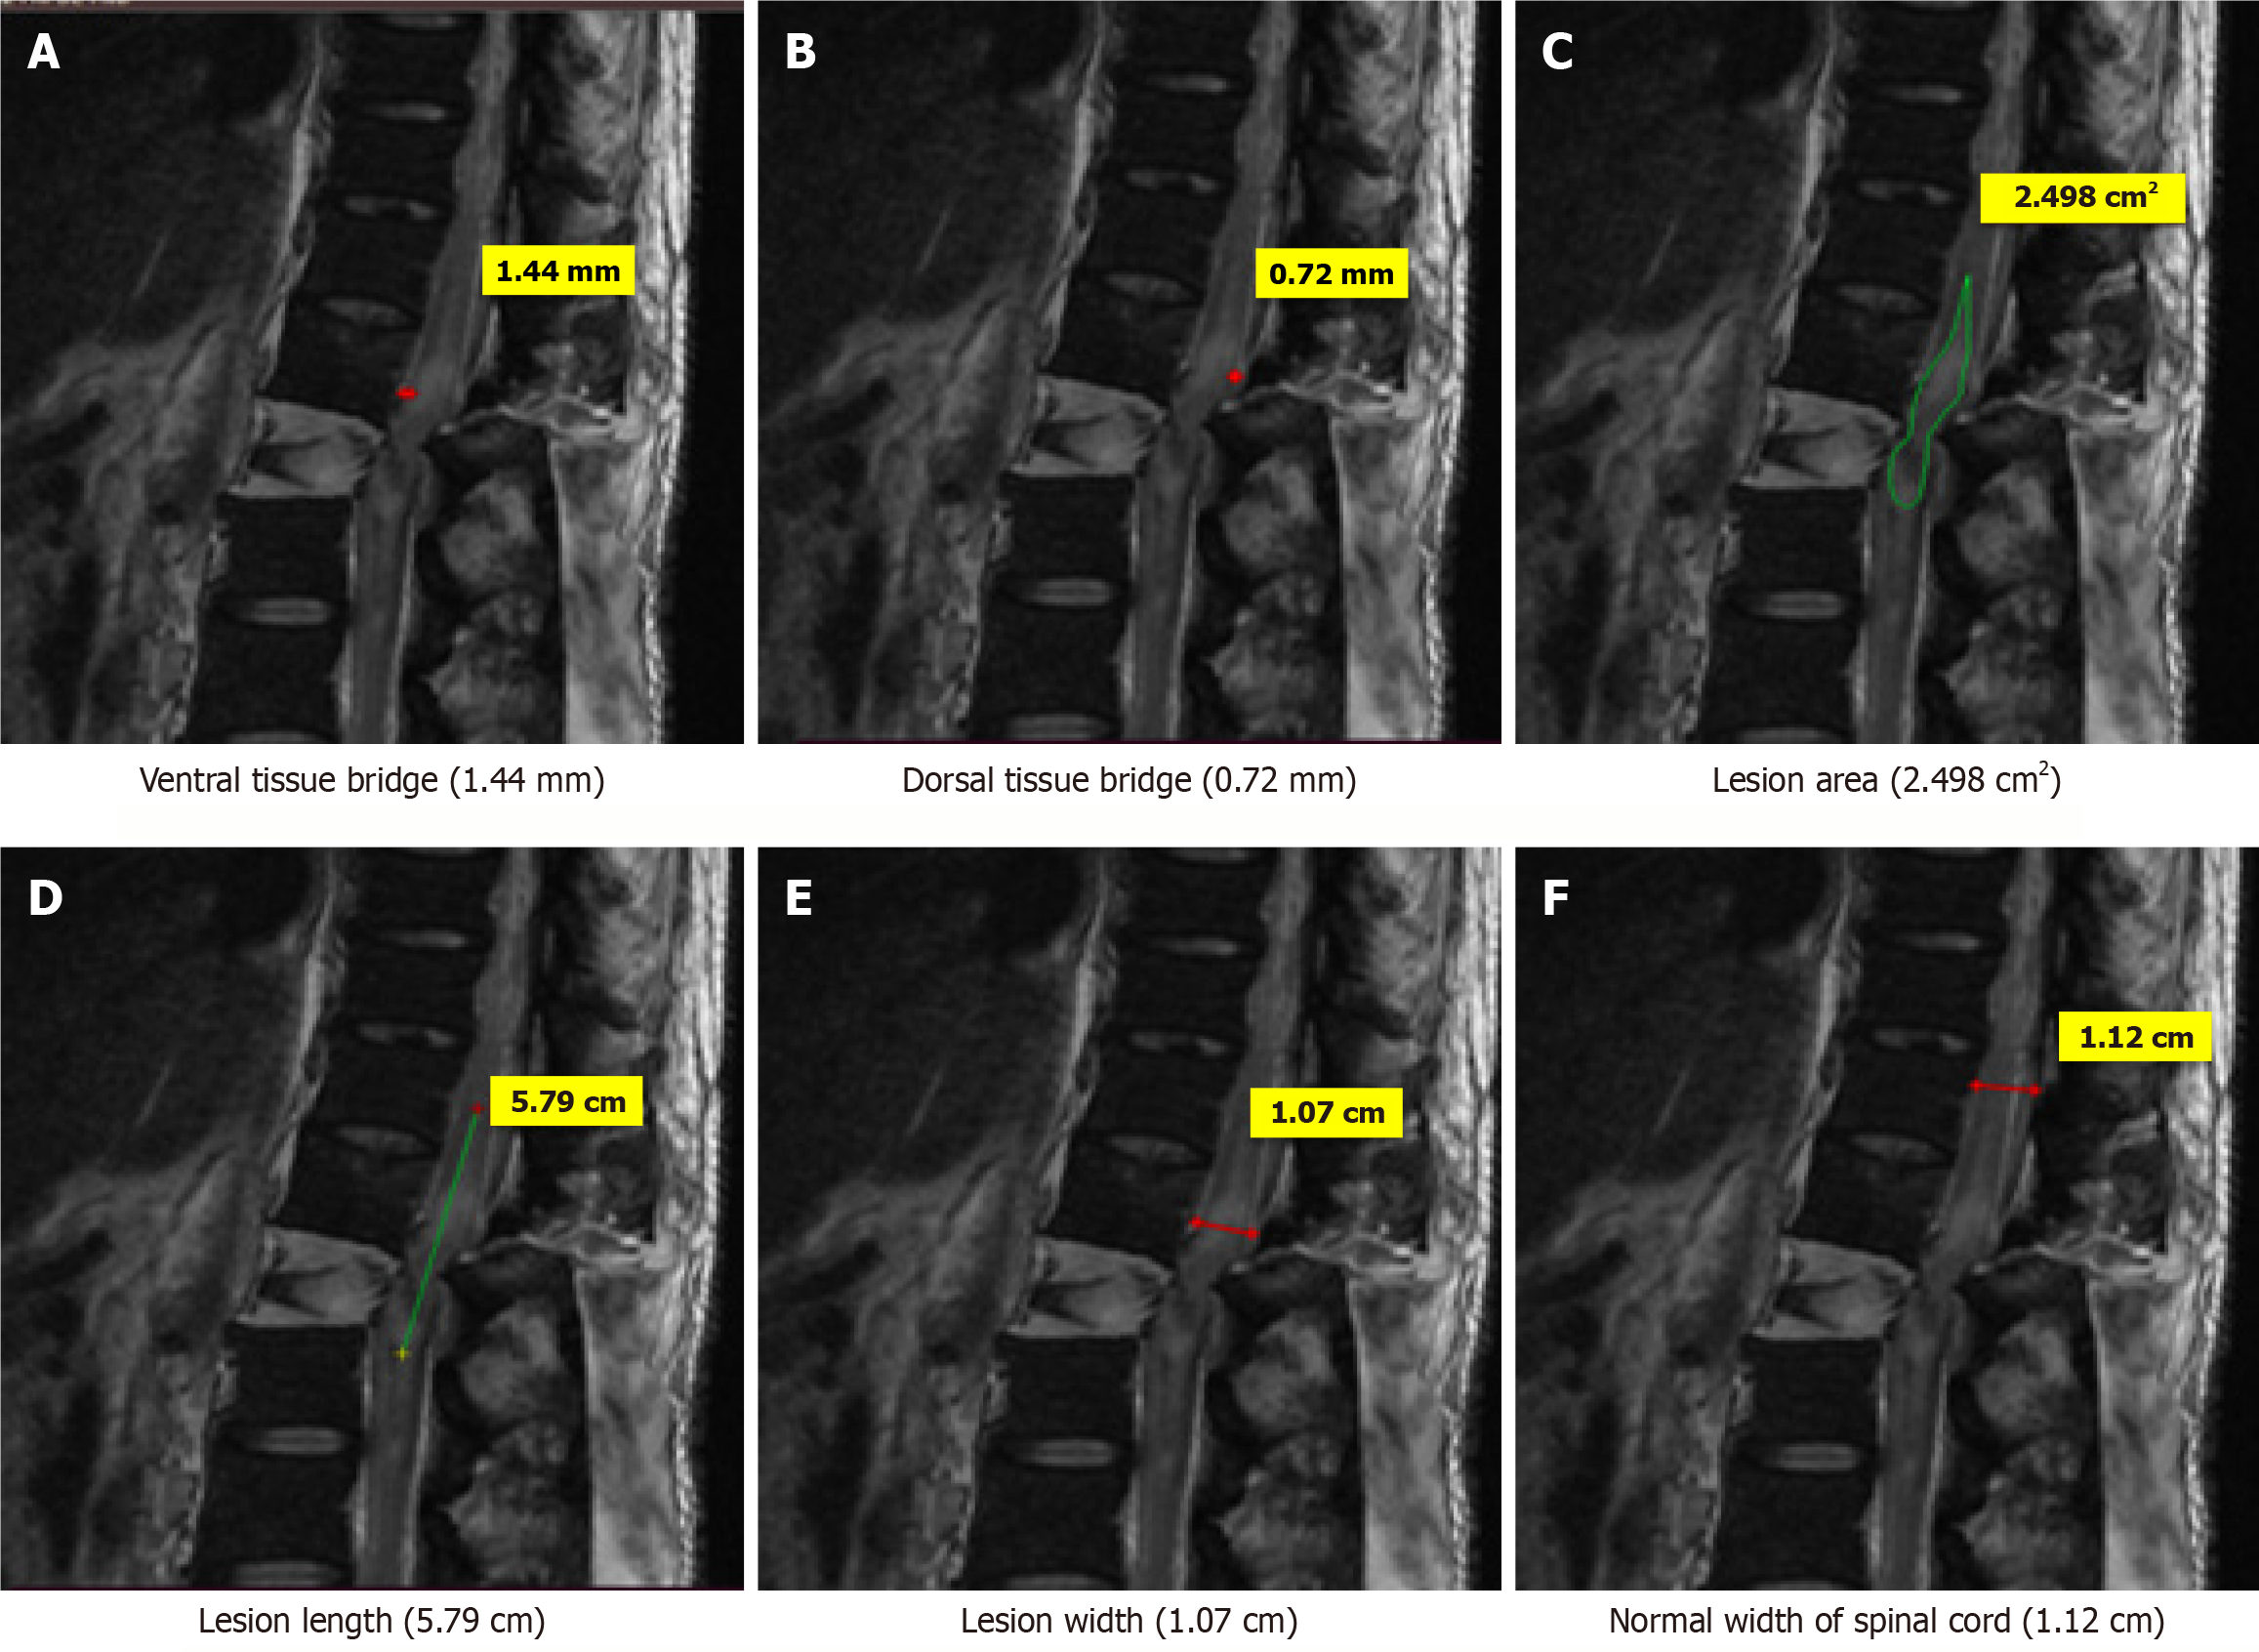

Figure 5 Magnetic resonance imaging T2-weighted sagittal image of a 34-years old patient who sustained trauma of thoracolumbar spine (D12-L1) with ASIA grade A.

A: Ventral tissue bridge (1.44 mm); B: Dorsal tissue bridge (0.72 mm); C: Lesion area (2.498 cm2); D: Lesion length (5.79 cm); E: Lesion width (1.07 cm); F: Normal width of spinal cord (1.12 cm).